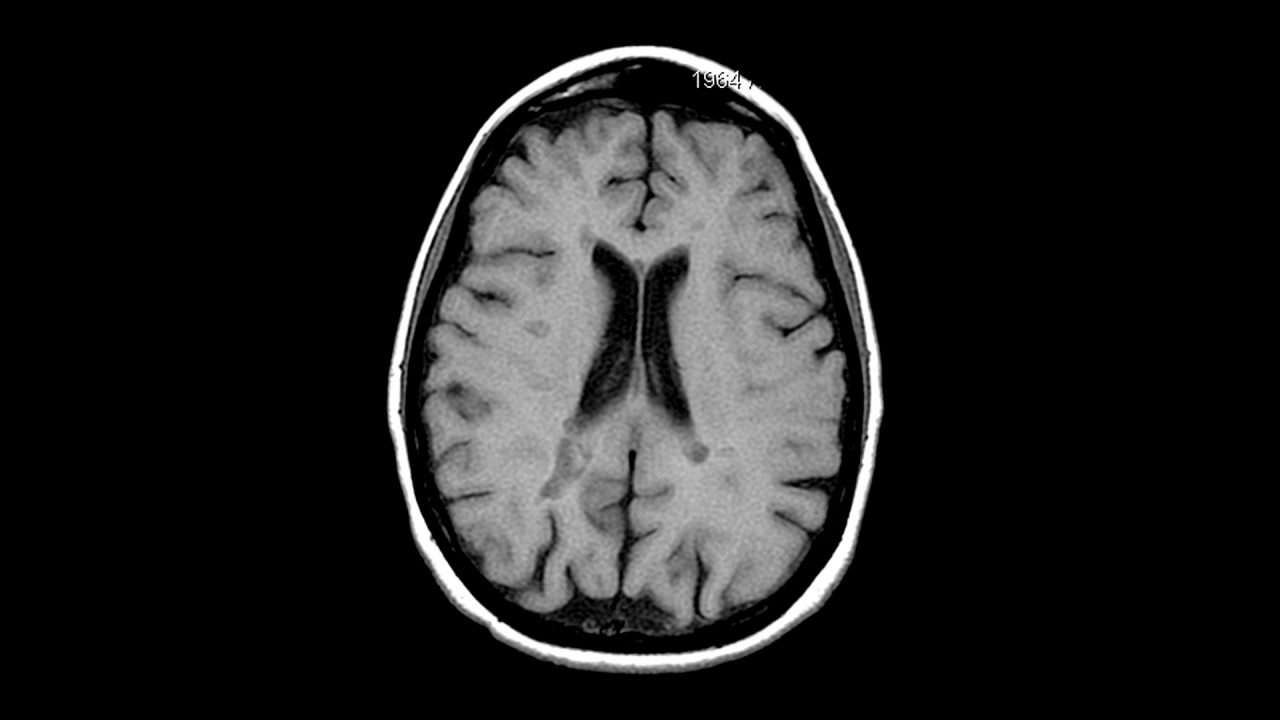

Prima, специјална медицинска AI, е обучена со преку 220.000 резултати од МР резултати и ги анализира скоро моментално, овозможувајќи дијагноза. Првите податоци тврдат за точност од над 97,5 % во повеќе од 50 дијагностички категории. Овој модел работи како vision-language пристап, разгледувајќи медицинска историја и МР сектори за сеопфатна анализа.

Во областа на здравството, модели како Prima ја зголемуваат брзината и доверливоста на анализа на медицински слики, овозможувајќи подобро поддршка на клиничките одлуки. GPT-5.3-Codex и Claude Opus 4.6 ја освојуваат софтверската сцена со побрза продукција на код и подобрени аналитички можности.